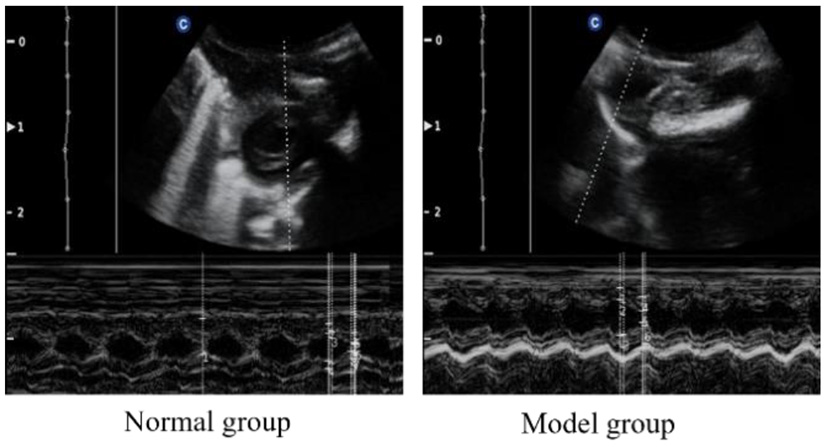

Doppler echocardiography

To verify the success of the model, we examined the cardiac function of the rats. The cardiac function of each rat was analyzed by echocardiography after modeling. As can be seen from Figure 1 and Table 2, compared with the normal group, the IVSD (mm) and LVEDD (mm) in the model group were significantly increased, the E/A < 1. This indicated that the diastolic function of the model rats was impaired.

Doppler echocardiography of normal and CHF-HKYd rats.